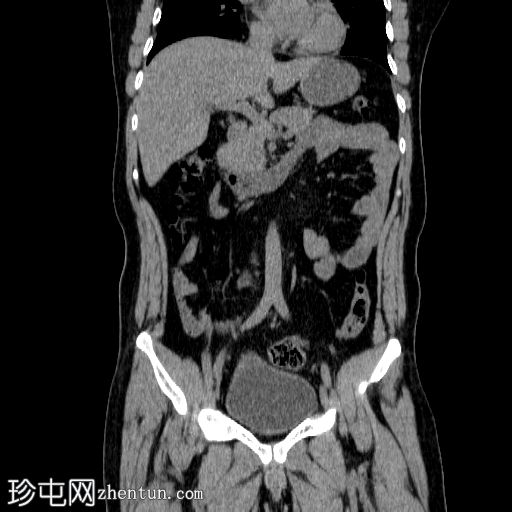

CT

轴位

平扫

右侧输尿管中段可见一卵圆形不透光结石,最大直径约6 mm,平均CT值约830 HU。该结石伴右侧近端输尿管及肾盂肾盏系统轻度扩张。

左侧输尿管轻度积水,未见明显梗阻性结石。

本病例展示了输尿管结石梗阻的典型CT表现,即上游反压改变。

未见肾周脂肪浸润、穹窿部破裂或尿瘤。